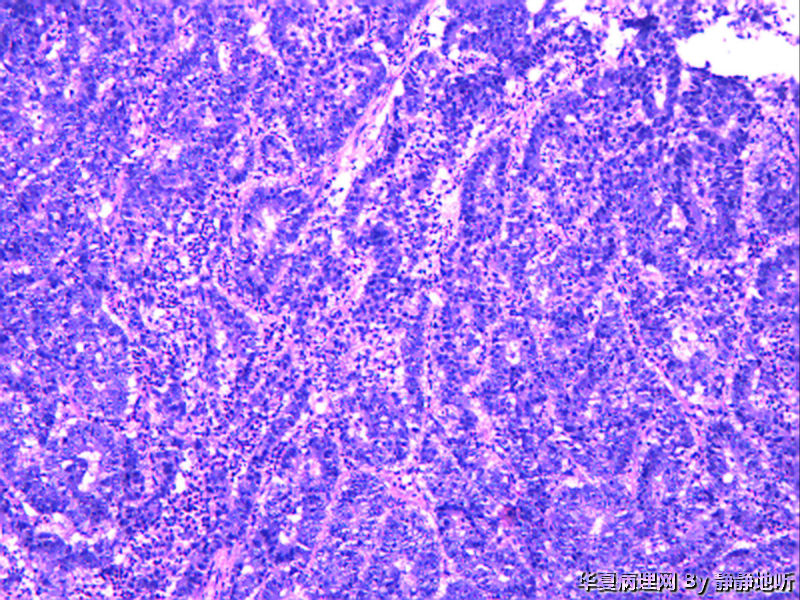

女性46岁,子宫峡部肿瘤,息肉样,体积3.5*4*3厘米,脱入宫颈,大体侵肌层。子宫肌壁明显增厚,大体似子宫腺肌症。

恶性:腺癌?类癌?

低分化子宫内膜样腺癌

子宫内膜样腺癌

恶性肿瘤,倾向癌肉瘤

恶性腺癌,分化差,希望有免疫组化鉴别下来源,需除外恶性苗勒混合瘤

免疫组化:ck7-    CEA-    ER -   PR -   CD10 -   Vimentin -   ki-67 约60%